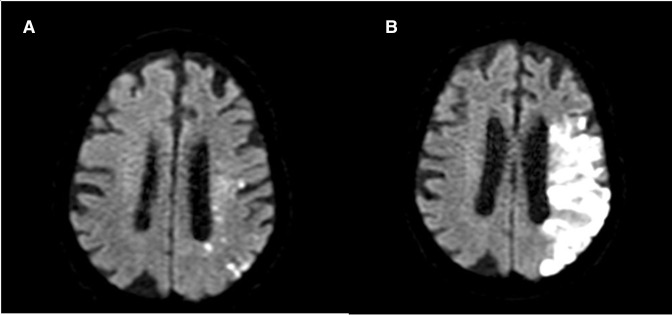

Background: The optimal time to commence anticoagulation in patients with atrial fibrillation (AF) after ischaemic stroke or transient ischaemic attack (TIA) is unclear, with guidelines differing in recommendations. A limitation of previous studies is the focus on clinically overt stroke, rather than radiologically obvious diffusion-weighted imaging ischaemic lesions. We aimed to quantify silent ischaemic lesions and haemorrhages on MRI at 1 month in patients commenced on early (<4 days) vs late (≥4 days) anticoagulation. We hypothesised that there would be fewer ischaemic lesions and more haemorrhages in the early anticoagulant group at 1-month MRI.

Methods: A prospective multicentre, observational cohort study was performed at 11 Australian stroke centres. Clinical and MRI data were collected at baseline and follow-up, with blinded imaging assessment performed by two authors. Timing of commencement of anticoagulation was at the discretion of the treating stroke physician.

Results: We recruited 276 patients of whom 208 met the eligibility criteria. The average age was 74.2 years (SD±10.63), and 79 (38%) patients were female. Median National Institute of Health Stroke Scale score was 5 (IQR 1-12). Median baseline ischaemic lesion volume was 5 mL (IQR 2-17). There were a greater number of new ischaemic lesions on follow-up MRI in patients commenced on anticoagulation ≥4 days after index event (17% vs 8%, p=0.04), but no difference in haemorrhage rates (22% vs 32%, p=0.10). Baseline ischaemic lesion volume of ≤5 mL was less likely to have a new haemorrhage at 1 month (p=0.02). There was no difference in haemorrhage rates in patients with an initial ischaemic lesion volume of >5 mL, regardless of anticoagulation timing.

Conclusion: Commencing anticoagulation <4 days after stroke or TIA is associated with fewer ischaemic lesions at 1 month in AF patients. There is no increased rate of haemorrhage with early anticoagulation. These results suggest that early anticoagulation after mild-to-moderate acute ischaemic stroke associated with AF might be safe, but randomised controlled studies are needed to inform clinical practice.